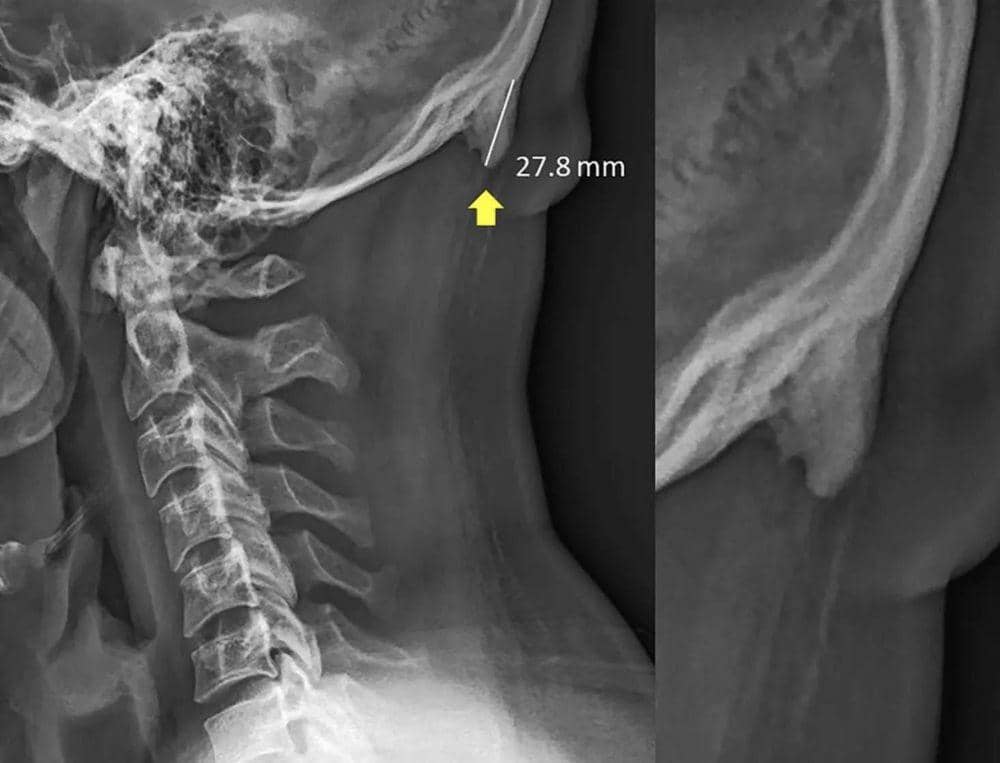

Tulang tambahan tersebut menurut peneliti terlihat seperti paruh burung, tanduk, dan kail. Sebenarnya tidak ada gejala khusus yang tampak atau dirasakan oleh orang yang memilikinya. Namun jika bagian leher atas diraba, akan terasa ada benjolan kecil yang keras. Selain itu, cara untuk mengetahuinya adalah melalui rontgen.